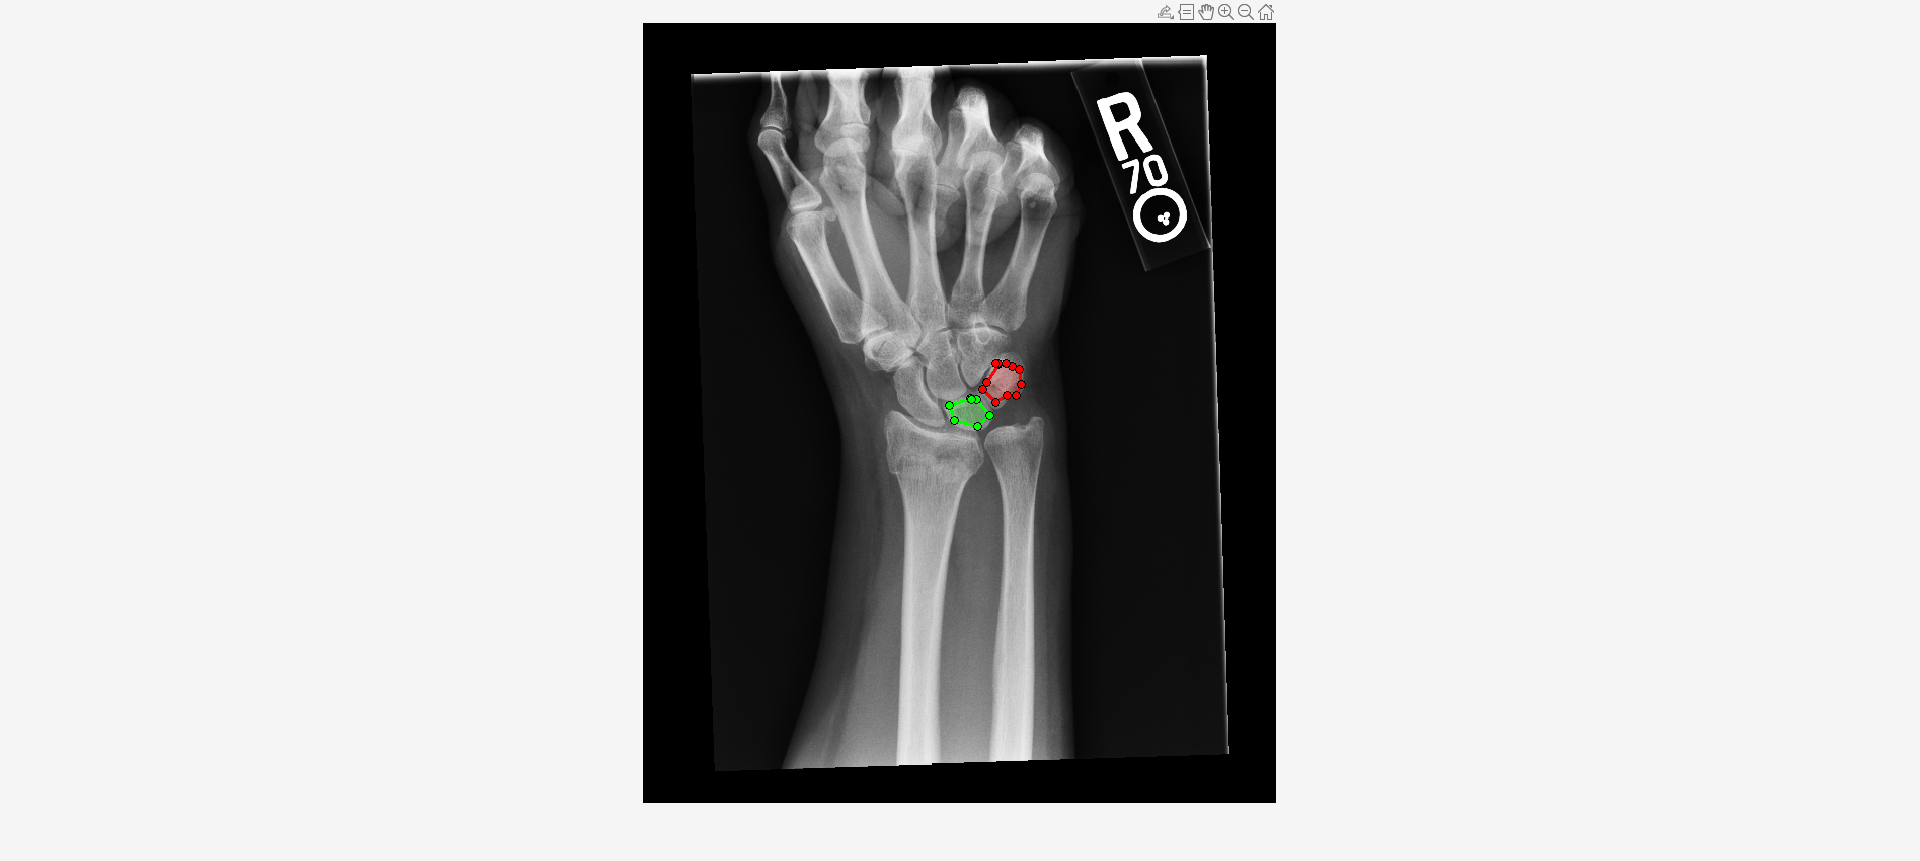

Load an X-ray image into the workspace as a medicalImage object. Visualize the image.

imshow(I,[])Draw two regions of interest (ROI) in the X-ray image. Create masks from the ROIs.

roi1 = drawassisted(Color="g"); roi2 = drawassisted(Color="r");

mask1 = createMask(roi1,I); mask2 = createMask(roi2,I);

Create an ROI label matrix, using different labels for the two ROIs. Create a medicalImage object of the ROI label data.

mask = zeros(size(I));

mask(mask1) = 1;

mask(mask2) = 2;

Compute shape features for both ROIs.

S = shapeFeatures(R)

S=2×24 table

"1" 54 54.427 135.84 2.5156 0.019243 0.13156 1.9662 0.5086 0.96618 0.18567 11.327 10.188 6.924 0 0.67962 0 0.63176 0.65158 NaN 0.91886 0.98182 0.99044 1.2498e+05

"2" 74 74.85 181.6 2.454 0.017061 0.10342 2.1304 0.46939 1.1304 0.24847 11.563 11.187 8.7535 0 0.78246 0 0.64598 0.66783 NaN 0.83862 0.93671 0.9552 1.8045e+05